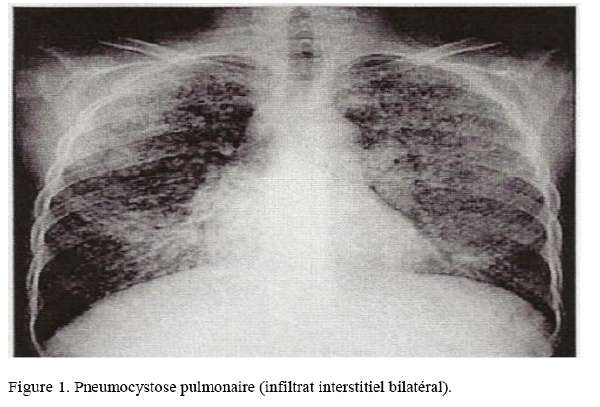

L’expression radiologique est très polymorphe : typiquement, on retrouve des opacités alvéolo-interstitielles bilatérales (Fig. 1), mais une radiographie de thorax normale n’élimine pas le diagnostic, surtout à un stade précoce. Plus rarement, sont mis en évidence des pseudos kystes ou un pneumothorax (un pneumothorax chez un patient VIH doit faire évoquer le diagnostic).